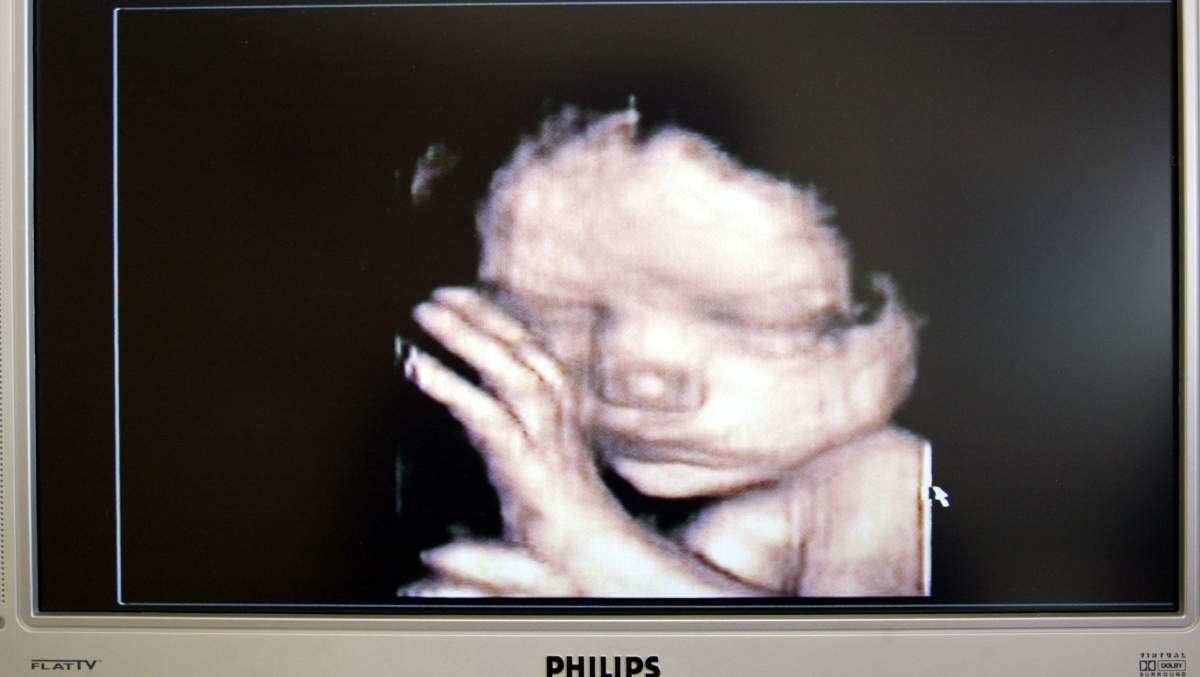

Catelynn Baltierra, una de las estrellas principales de Mami adolescente OG confirmó que estaba embarazada. Catelynn y Tyler han estado hablando de querer tener un niño y han hablado de tratar de quedar embarazada en la temporada actual de la serie MTV. El embarazo de Catelynn viene después de que trágicamente percató en días de Acción de Gracias después de que ella y Tyler convencieron. Fue la segunda vez que Catelynn sufrió un aborto.

“Definitivamente me sorprendió que nos quedamos embarazadas tan rápido con este bebé!” Catelynn dijo a Celebuzz en una entrevista exclusiva el 22 de febrero. “Pero estamos tan emocionados”. Tyler, de 28 años, estaba sorprendido por las noticias. Al principio, no lo creía, dijo el nativo de Michigan. Acabo de darle la prueba positiva. Tyler se mantuvo dudoso sobre el embarazo de su esposa hasta que se perdió su período y luego tomó otra prueba, que volvió positiva. Las cámaras de MTV estaban allí cuando Catelynn y Tyler se enteraron de que estaban esperando otro bebé, pero la pareja incluso escondió las noticias de los productores inicialmente. “[Nosotros] esperábamos hasta que yo estaba más adelante para mencionarlo en el espectáculo!” explicó.

La estrella anunció las noticias sobre las redes sociales compartiendo una foto de la hija de 6 años Nova y la hija de 2 años Vaeda con una señal que decía que serían hermanas grandes en 27 semanas. Catelynn y Tyler también son los padres de Carly Davis, a quien colocaron para su adopción cuando nació. Tyler compartió un post similar. “No puedo esperar otra hermosa bendición”, escribió en Instagram. “El arco iris valía la pena. El bebé Baltierra vendrá pronto. Fellow Adolescente mamá papá Cory Wharton llegó a Tyler para celebrar las buenas noticias. Felicitaciones por el Sí, escribió.